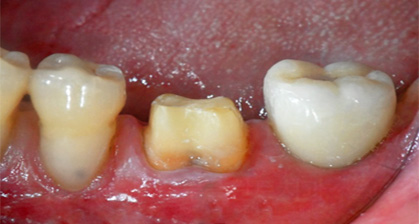

당일 완성 지르코니아 크라운

치과당일치료 하루플란트치과의 혁신적인 하루완성 클리닉

지르코니아 크라운은 내구성이 강하고

자연스러운 색감을 가진 보철물로,

미적 감각과 기능성을 동시에 만족시키는데요.

하루플란트치과에서는 최신 기술과 장비를 활용하여

지르코니아 크라운을 내원 당일 제작합니다.

기존에 8시간가량 소요되는 제작 시간을

2시간으로 줄이고 임시 치아 과정 없이

당일에 최종 보철물을 장착하여

바로 일상생활에 복귀할 수 있도록 돕습니다.

당일 완성 앞니 지르코니아 크라운

당일 완성 어금니 지르코니아 크라운